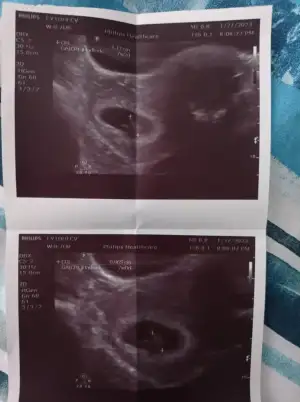

Ben de gece uyaniyorum kusuyorum 2 saat falan uyuyamıyorum sabah da ise geliyorum bayılacam kalcam bi güngecenin bu saatinde mide bulantısı denen illet yüzünden uyandım kramp giriyor artık yemek u

yiyemediğim için ne zormuş arkadaş ayno durumda olan varmı acaba